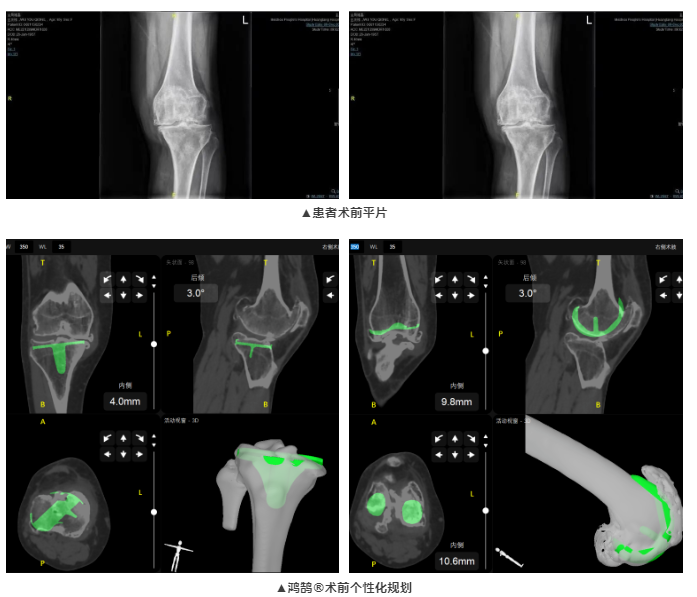

梅州市人民醫(yī)院成功完成首例鴻鵠?機(jī)器人輔助人工全膝關(guān)節(jié)置換手術(shù),鴻鵠?精準(zhǔn)、個(gè)性的術(shù)前3D規(guī)劃功能,協(xié)助醫(yī)生掌握更多患者信息,為患者制定個(gè)性化假體植入手術(shù)計(jì)劃

患者為65歲女性,雙膝疼痛20年,近日疼痛加劇,就診于梅州市人民醫(yī)院。術(shù)前經(jīng)檢查發(fā)現(xiàn)雙膝關(guān)節(jié)內(nèi)翻畸形,診斷為雙膝關(guān)節(jié)骨性關(guān)節(jié)炎。術(shù)前患者雙膝疼痛,導(dǎo)致行走功能受到明顯阻礙,嚴(yán)重影響生活質(zhì)量。廖紅興博士團(tuán)隊(duì)經(jīng)綜合評(píng)估,決定行鴻鵠?骨科手術(shù)機(jī)器人輔助全膝關(guān)節(jié)置換術(shù)。

本次全膝關(guān)節(jié)置換術(shù),術(shù)前,廖紅興博士團(tuán)隊(duì)通過鴻鵠?為患者進(jìn)行膝關(guān)節(jié)CT圖像三維重建,制定符合患者生理特征的個(gè)性化假體安裝方案,提高后續(xù)手術(shù)治療效率;術(shù)中,鴻鵠?引導(dǎo)完成機(jī)械臂注冊(cè)和骨注冊(cè),機(jī)械臂精準(zhǔn)定位到預(yù)期規(guī)劃位置,一體化截骨工具輔助醫(yī)生完成股骨脛骨截骨,進(jìn)而實(shí)現(xiàn)假體精確安放。